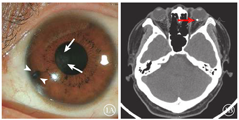

患者男,44岁。因慢性头痛行磁共振成像(MRI)检查期间左眼突发视力下降至光感到中山大学中山眼科中心就诊。眼部检查:右眼视力0.8,左眼视力光感。右眼眼压20 mmHg(1 mmHg=0.133 kPa ),左眼眼压14 mmHg。裂隙灯显微镜检查,左眼8点时钟位虹膜组织缺损,为陈旧虹膜穿通伤,同时伴有晶状体局部混浊(图1A)。右眼眼前节及眼底检查未见异常。眼底检查,左眼可见大量玻璃体积血。右眼眼底检查未见异常体征。追问病史,患者诉2年前驾驶摩托车穿越工地时被沙土飞溅至脸上,未行任何诊治。CT检查,左眼视盘旁结节状高密度影(图1B)。既往史无其他特殊,否认家族史。诊断:左眼玻璃体积血、左眼球内异物、左眼外伤性白内障、左眼虹膜缺损、左眼陈旧性眼球穿通伤。给予玻璃体切切割联合球内异物取出手术治疗。手术中清除玻璃体积血后,可见该球内异物为银白色磁性金属异物(图2)。通过恒磁接力取出该异物后其表面氧化变黑,宽度约为1 mm。手术后行常规局部抗炎治疗,规律复查,无并发症产生。手术后3个月复查,左眼视力可达0.8 ;眼前节体征与手术前无变化;视网膜平复,既往异物所在位置有瘢痕形成及少许色素改变。